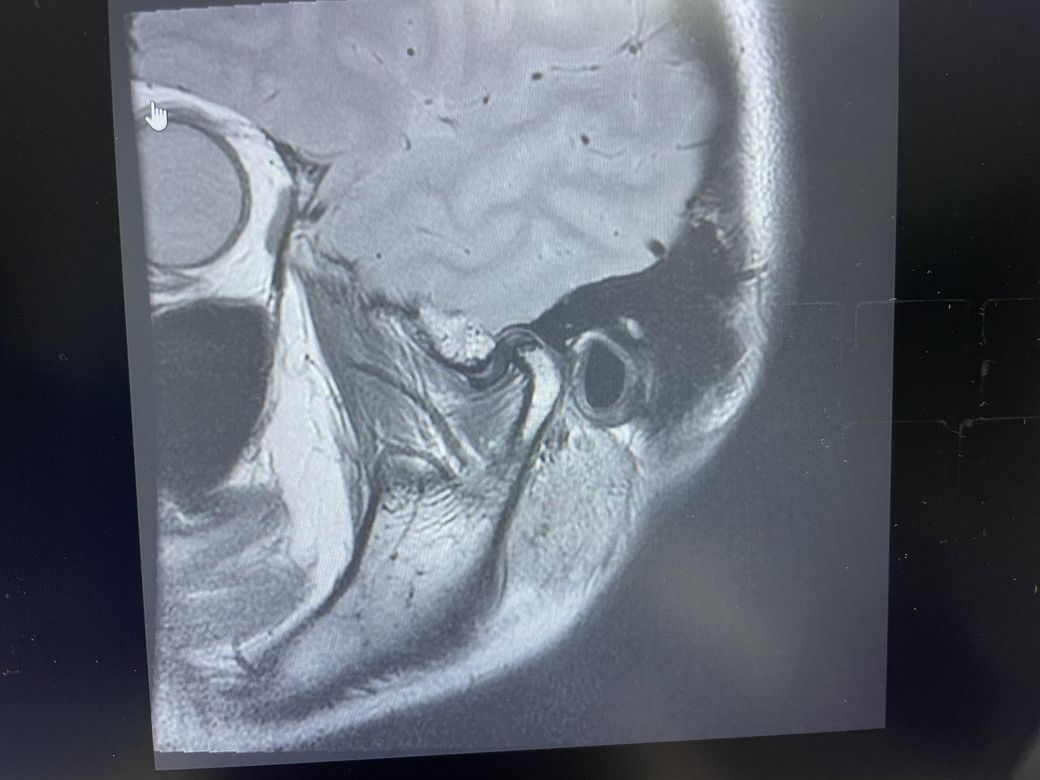

구강내과 턱 MRI 어느 사진이 우측? 좌측?인지 어떻게 보나요? 디스크 두꺼워짐 심한가요?ㅜ

구강내과 턱 MRI 사진 보는데 귀 위치가 다 똑같아서요

어느 사진이 우측? 좌측?인지 어떻게 보나요?

그리고 사진 상 디스크 두꺼워짐 심한가요?ㅜ

현재 사진만으로는 정확히 왼쪽이나 오른쪽이다 라고 할 수 없습니다. 이는 데이터 상의 reference가 필요하며 보통은 해당 부위가 질문자님 기준으로 좌측일 가능성이 가장 크나 이는 좌우 반전을 할 수 있기 때문에 무조건 좌측이라고 할 수 없습니다. 현재 개구시와 폐구시에 보았을 때 condyle (아래턱 부위의 일부)가 disc를 넘어가지 못하고 있으며 이러한 경우 개구제한이 있거나 넘어가더라도 소리가 나면서 넘어갈 수 있습니다. 일부 염증도 보이고 있으므로 내과적인 치료를 하셔야 할 것으로 보입니다.